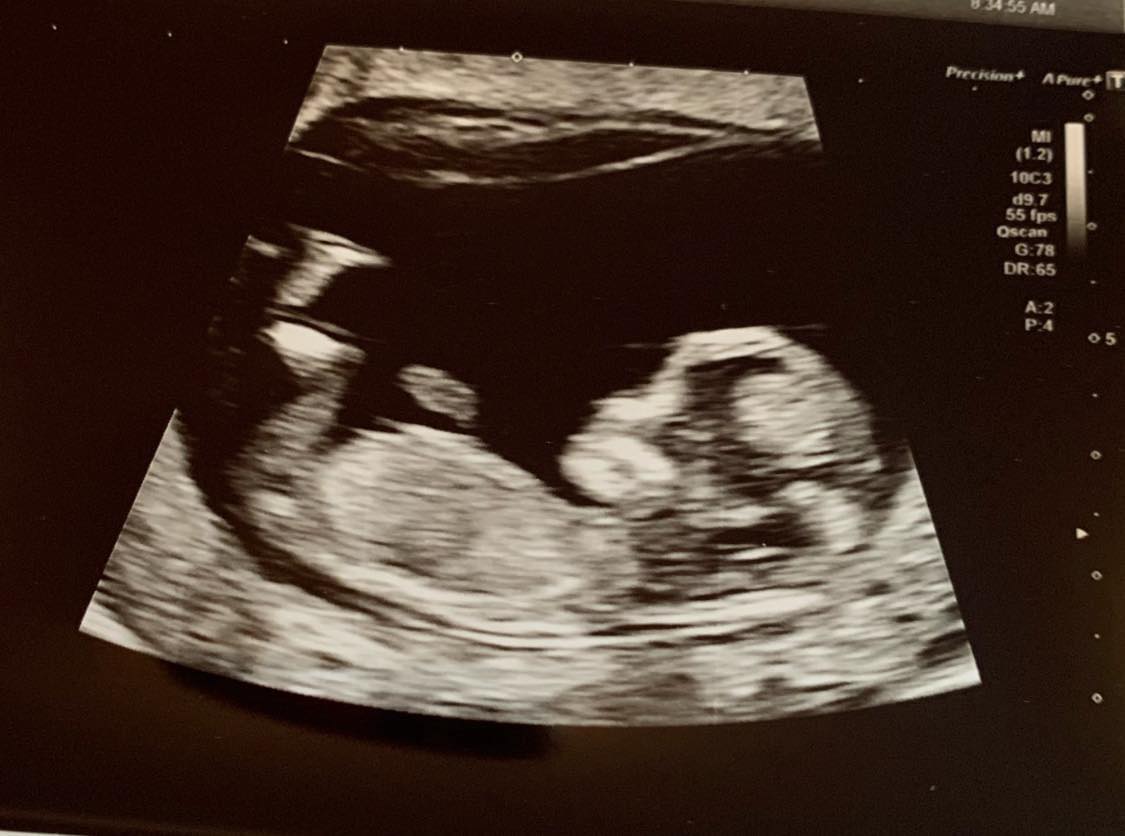

为此,艾玛决定和戴比一起为内森送上一个惊喜。她们参照怀孕12周的超声波扫描照片,花数星期时间手工制成了一幅立体刺绣,看起来跟超声波扫描非常相像。

直到12月11日,内森收到了艾玛送上的超声波扫描刺绣版,他指出直到刺绣完成,艾玛才让他知道。他拿着刺绣时显得很激动,花了几分钟时间细心触摸,感受孩子的模样。